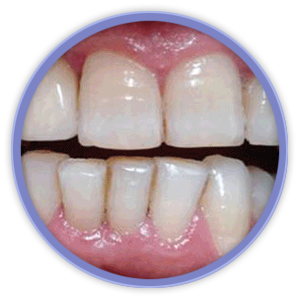

El aspecto más revolucionario en este ámbito fue la aparición de los implantes dentales que son unos pequeños bloques de titanio, con forma de raíz dental, que se insertan dentro del hueso mandibular o maxilar del paciente y sirven de sujeción para dentaduras, puentes o coronas, mejorando así la calidad de vida y aumentando las posibilidades de tratamiento de los pacientes.

Mediante técnicas de rehabilitación en un solo día, hacemos posible que el paciente salga de la consulta con los implantes y sus dientes, provisionales fijos, colocados.

La magnificación de la imagen mediante lupas o microscopio dental nos permiten niveles de acabado y de precisión mucho más exigentes. Actualmente la importancia de la estética gingival (encías), ha obligado a desarrollar técnicas de regeneración de hueso y tejidos blandos, que complementan a las cirugías de implantes entre otras.